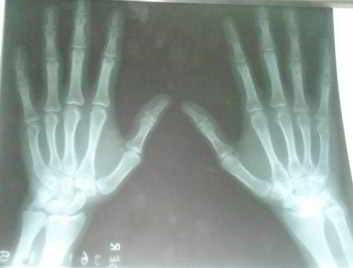

Figura 1